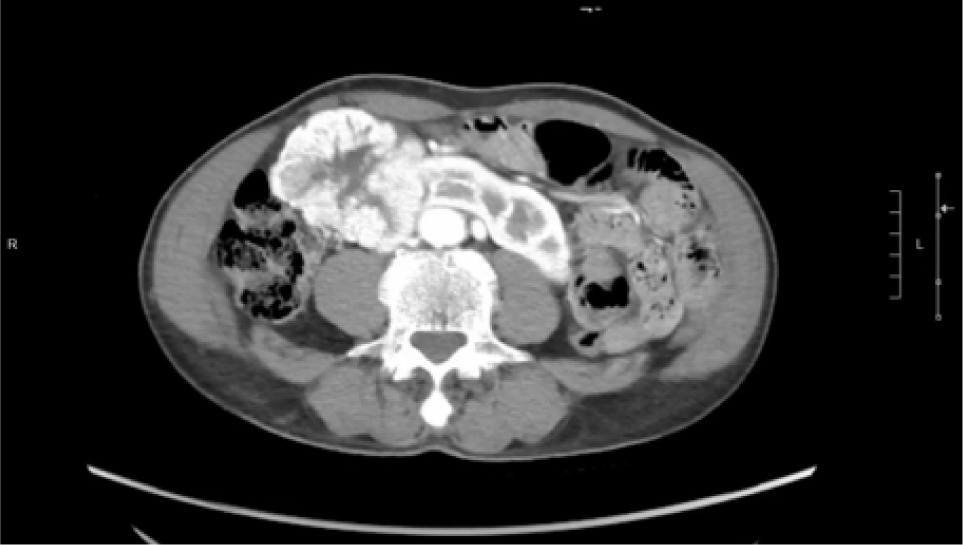

Bilateral RP and ureteric catheterization were first performed for the identification of the hila and calyces of the HSK (Figures 4 & 5). A lower midline laparotomy was performed. The tumor was identified, measuring 7 cm in diameter (Figure 6). Careful dissection of complex hilar structure was performed. Two renal arteries and two renal veins supplying the right side were identified and slung (Figure 7). The tumor was resected with artery clamping (Figure 8). The right lateral calyx of the pelvicalyceal (PC) system was involved and resected. The PC system was closed with 3/O PDS. Renorrhaphy was completed with 3/O V-Loc, and parenchyma was closed with 2/O V-Loc. Ischemic time was 20 minutes, and total operation time was 332 minutes. Blood loss was 420 mL. The patient had completed 1 week of levofloxacin and was discharged on postoperative day 6 with one kick of fever that spontaneously subsided.

Figure 4: Left renal pelvis.

Figure 5: Right renal pelvis.

Moreover, challenges may arise when conventional imaging methods such as CT scans and 3D reconstructions fail to provide a clear depiction of the renal pelvis, leading to uncertainties regarding its boundaries and internal structure. In such instances, intraoperative strategies become crucial, including RP of the renal pelvis and collecting system to guide surgical decision-making. In addition, the intraoperative injection of the dye can be utilized to confirm the precise location of the renal pelvis, aiding in surgical navigation. Real-time imaging techniques using fluoroscopy at key junctures in the procedure, such as before making incisions, prior to tumor removal, and after closing the renal pelvis, offer valuable insights and guidance in managing the unclear structures effectively. Employing on-table surgical planning based on real-time imaging data becomes essential in adapting to unforeseen challenges and ensuring optimal treatment outcomes for RCC within the unique anatomical context of an HSK.

We have effectively utilized intraoperative RP to enhance surgical precision in mapping the intricate anatomy of the renal pelvis. Unlike previous methods relying on CT scans and 3D reconstructions, which often fall short in detailing the exact drainage pathways from the renal pelvis to the ureters in cases of HSKs, intraoperative RP provides invaluable insights. This technique enables our surgical team to gain a comprehensive understanding of the renal drainage system, crucial for ensuring that the renal pelvis remains open and connected to the appropriate structures following partial nephrectomy. In essence, intraoperative RP serves as a vital and secure tool for urologists, empowering them to navigate the complexities surrounding anomalous renal pelvis structures with precision, thereby mitigating the risks of postoperative complications.